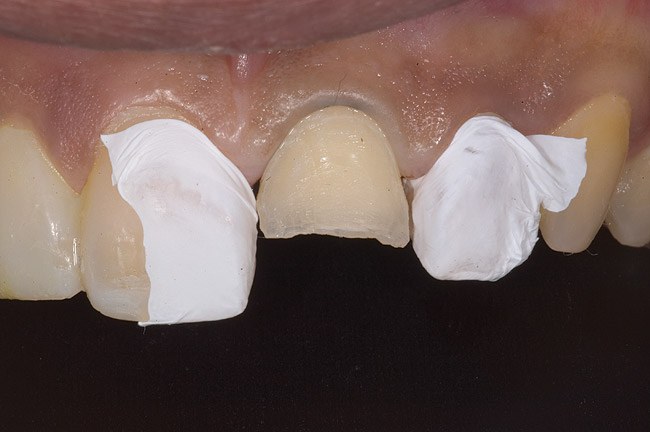

Figure 9: Tooth No. 9 minimally prepared for resin layering on the labial surface.

Figure 9

Figure 10  Tooth No. 9 with no preparation on the palatal surface to restore lost form with bonding resin.

Figure 10